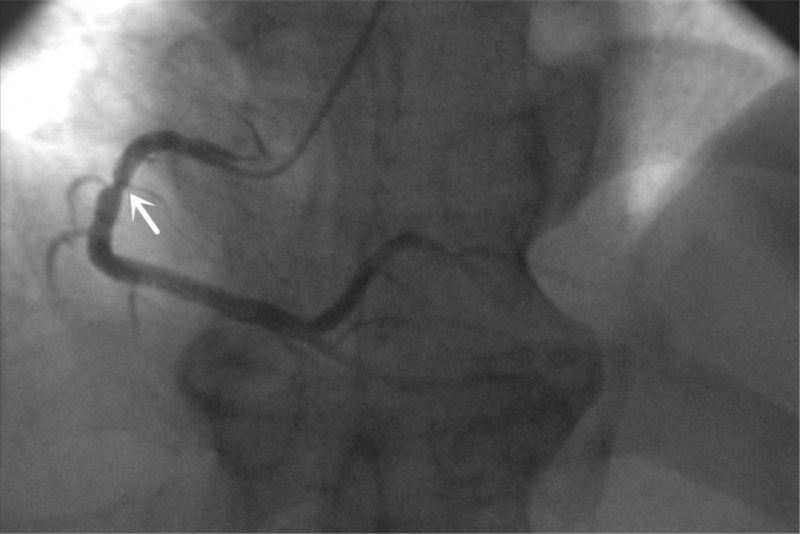

冠状动脉造影检查提示:右冠近段管状狭窄病变。

压力微导管血流储备分数测定显示:病变两端FFR值为0.88。